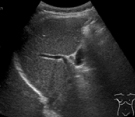

■腹部超音波検査

腹部超音波検査は、肝臓・胆嚢・胆管・膵臓・腎臓・脾臓などの上腹部領域を中心に検査を行っています。その他には大腸・虫垂などの消化管領域、および前立腺・膀胱・子宮・卵巣などの下腹部領域も検査する場合があります。仰向けだけではなく、側臥位や座位などの体位変換を行っていただく場合があります。

肝臓

胆嚢

膵臓

腎臓